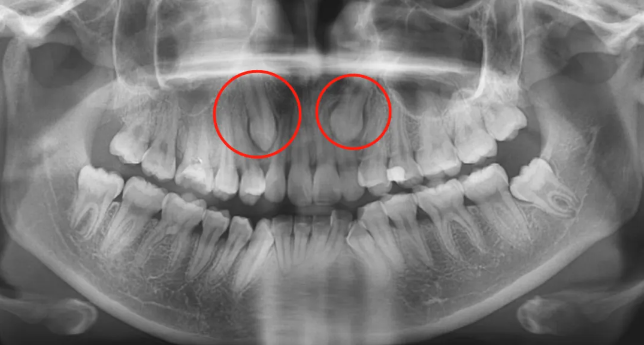

△全口牙齿一般有28-32颗,在牙片上从中间牙齿往后数第八颗就是智齿。

🔎儿童恒牙萌出

🔎牙齿不齐